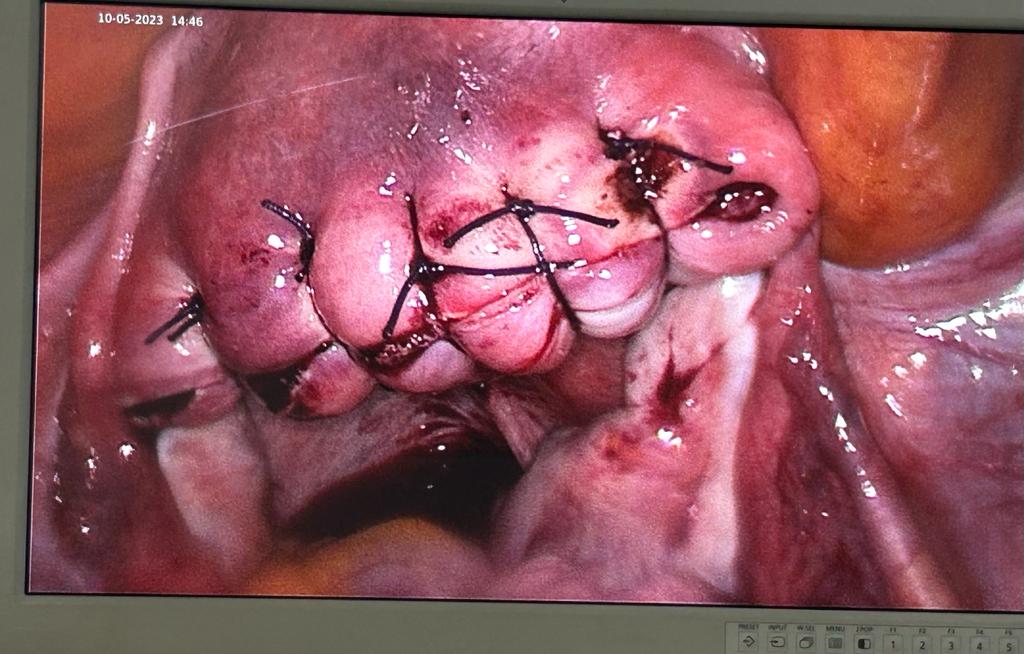

Laparoscopic Removal of Myoma in infertile couple